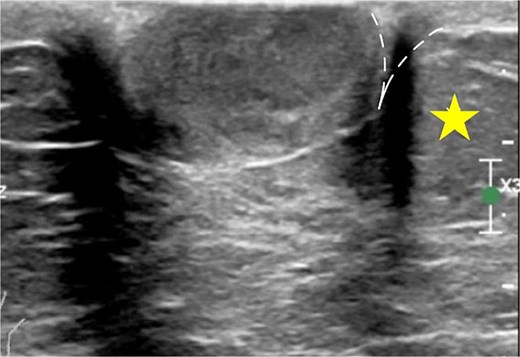

A 75-year-old female patient presented with left nipple pain and nipple discharge for one year. She denied any family history of breast or ovarian cancer, as well as any use of tobacco or hormonal drugs. Physical examination revealed a 1.5 × 1.5 cm firm, tender, and well-circumscribed mass at the left nipple, without skin or nipple retraction. The ipsilateral axillary lymph node was not palpable. While mammography was unremarkable, ultrasonography revealed a 1.7 × 1.5 cm oval, inhomogeneous hypoechoic mass with a predominantly vascularized rim (Fig. 1). An inflammatory mass, classified as BI-RADS 3, was considered.

Ultrasonographic finding of left nipple mass, (A) before applying color Doppler mode and (B) after applying color Doppler mode.